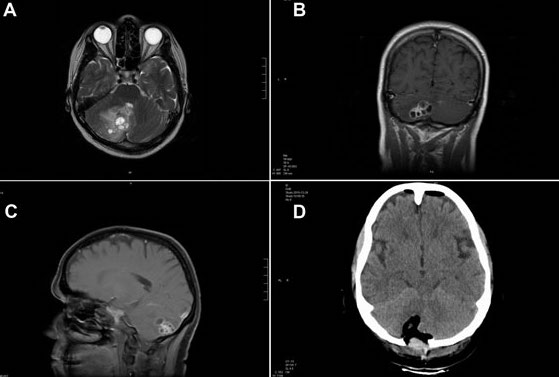

A brain tumor occurs when abnormal cells form within the brain. Are there any other risks? After a tiny hole is drilled into the skull, a small needle is placed into the.

This can be because they increase the pressure inside the malignant brain tumours can spread from where they started into surrounding brain tissue, causing pressure and.

Michael brisman, a neurosurgeon with nspc brain & spine surgery on long island, ny. Don't assume you have a brain tumor just because you have some of the your doctor will consider several things in deciding how to treat your brain tumor, including Although a brain tumor rarely causes headaches, someone with no history of headaches who develops them should be seen by a doctor. Brain tumors can affect brain function if they grow large enough to press on surrounding nerves how is a brain tumor diagnosed?